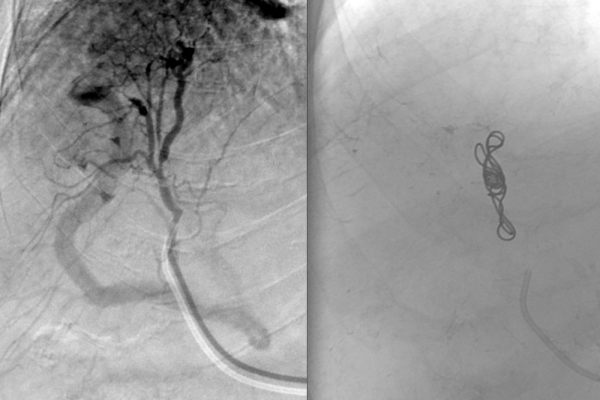

♦ Αιμορραγίες

Τραυματική κάκωση αγγείων

Συνοπτικά υπό την καθοδήγηση του αγγειογράφου, αναγνωρίζεταιτο παθολογικό αγγείο-αγγεία και με ειδικούς καθετήρες και μικροκαθετήρες, διοχετεύονται εμβολικά υλικάόπως μικροσφαιρίδια ή coils, ώστε να αποφραχθεί ή να μειωθεί η παθολογική αγγείωση.